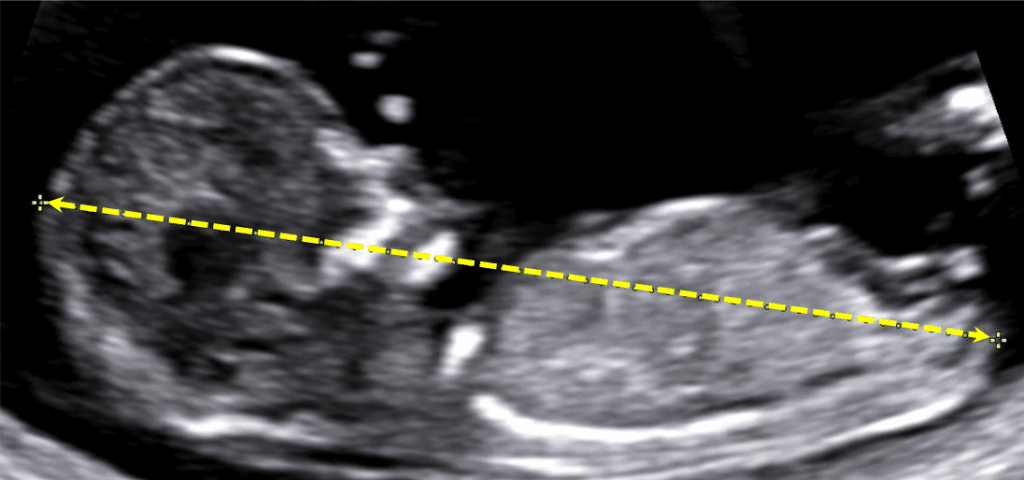

O CCN é definido como a reta mais longa do embrião, da margem externa do polo cefálico até a região da nádega. Geralmente, um comprimento de pelo menos 5 mm permite a visualização rotineira do embrião, embora embriões menores, entre 2 e 3 mm, também possam ser vistos.

Comprimento cabeça-nádega (CCN)

No primeiro trimestre da gravidez, a avaliação ultrassonográfica do comprimento cabeça-nádega (CCN) é considerada o método mais preciso para estimar a idade gestacional. Enquanto o tamanho do saco gestacional pode ser medido inicialmente para essa avaliação, o CCN se mostra um indicador mais confiável.

Quando o embrião atinge um estágio em que o pólo embrionário é evidente no saco gestacional, o CCN é medido para determinar a data provável do parto (DPP). Essa primeira medição do CCN estabelece a DPP do paciente, que não é alterada com base em biometrias subsequentes.

- Entre 6 e 7 semanas de gestação, quando o embrião é visível e mensurável, o CCN é o parâmetro biométrico mais preciso para a datação da gravidez, com uma precisão de ±5 dias;

- Quando o CCN é inferior a 25 mm, a idade gestacional em dias é calculada somando-se o valor do CCN (em mm) a 42;